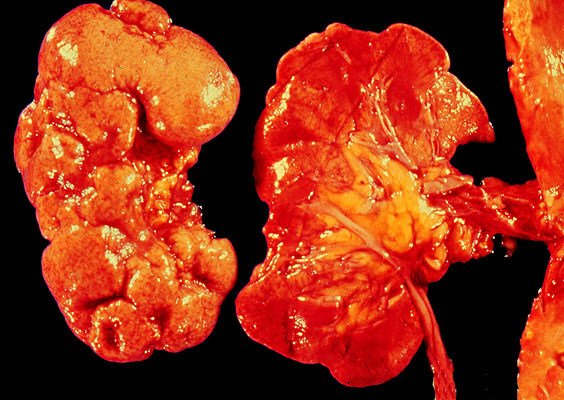

Chronic pyelonephritis, gross

Severely scarred kidney.